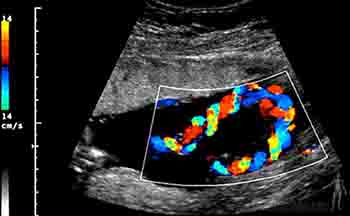

Las células foliculares forman la zona pelúcida, una capa glicoproteica que las separa del ovocito. Si bien esta es una membrana continua, contiene prolongaciones de las células foliculares que se ponen en contacto con el ovocito. Las células que rodean a la zona pelúcida y al ovocito primario constituyen el grupo de células de la granulosa. La primera capa de la granulosa que toma ontacto con el ovocito es la corona radiada. Las células de la granulosa, la zona pelúcida y el ovocito primario conforman así el denominado folículo primario (Figuras 2-2a y b).

Al continuar la estimulación de la hormona foliculoestimulante las células de la granulosa, que van aumentando en número, comienzan a tener espacios entre sí y determinan la conformación de una cavidad denominada antro folicular, conformando un folículo secundario. Finalmente, el folículo secundario constituye una gran cavidad o antro que se va haciendo cada vez más amplia y determina que este grupo de células de la granulosa, con su zona pelúcida y con su ovocito primario, sean desplazadas a un extremo del folículo. Las células de la granulosa, a su vez, constituyen el denominado cúmulo oóforo. Un folículo que presenta estas características, o sea, que tiene un cúmulo oóforo, posee células granulosas en la periferia y un tejido conjuntivo ovárico especializado, llamado teca, se denomina folículo terciario o de Graaf, y es el que será ovulado.